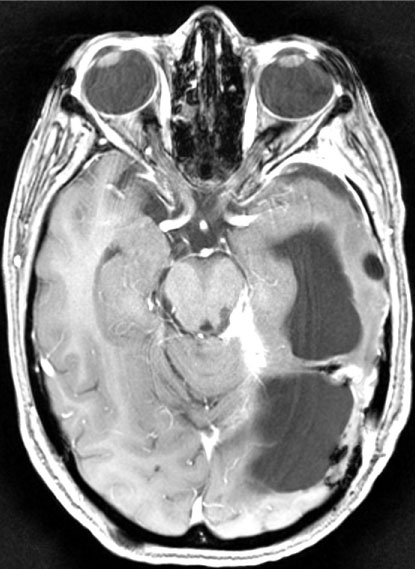

The authors hereby present a case managed by a multi-disciplinary team involving a huge intracranial meningioma. This patient is a 36-year-old female which presented to our institution with headaches, gait disturbances, visual disturbances and dizziness which began 3 months prior to her admission (Figure 1). Her medical history is noticeable for leukemia at age 6 which was treated with chemotherapy and radiation to the head, with no current active malignancy. Upon admission the patient underwent a CT scan and a subsequent MRI which revealed a highly vascularized, gigantic 9.3 × 6.1 cm left supra and infra-tentorial brain lesion suspected for a meningioma causing severe mass effect.

Figure 1: A gigantic left supra and infra-tentorial meningioma in a 36-year-old female. Notice the blood vessels supplying the tumor. View Figure 1